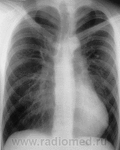

Вот тоже, возможно по теме...

Chest X-ray Atlas

Воронкообразная деформация грудной клетки.